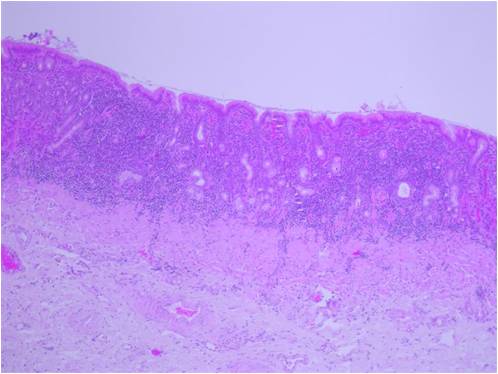

Maladie digestive du furet

Les furets sont très sujets aux maladies digestives. Leurs selles peuvent être de consistance plus ou moins moulées mais parfois on notera des diarrhées régulières. C'est ce que l'on appelle les maladies digestives chroniques du furet. Il existe de très nombreuses causes à cela, elles peuvent être d'origine alimentaire, inflammatoire, tumorale (lymphome), parasitaire ou encore bactérienne (hélicobacter). Le diagnostic se fait principalement par prise de sang, échographie et par endoscopie digestive. Cette dernière permet de faire des prélèvements pour confirmer le diagnostic et ajuster le traitement. La maladie digestive peut s'étendre au foie.

Devaux, L., Huynh, M., Hernandez, J. & Nicolier, A. Upper gastrointestinal endoscopy in ferret and the histological assessment of the endoscopic biopsies. Vet Rec 178, 96, doi:10.1136/vr.103164 (2016).